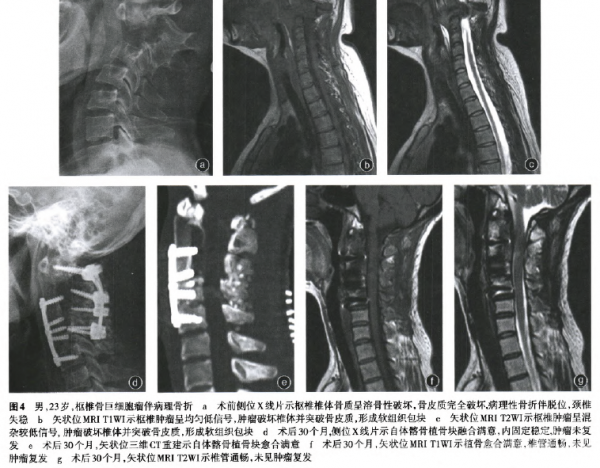

三、重建效果

3例骨包壳完整植入,B-TCP人工骨颗粒的患者,术后第3个月可见植骨颗粒边界和内部结构模糊,术后12个月可见植骨中心区域植骨颗粒融合成片。随着时间推移,植骨颗粒的成骨降解均满意,形成自身骨质(图2)。2例取髂骨结构性植骨的患者,术后6个月可见植骨块与齿突、C,椎体融合,术后12个月达到完全愈合(图3)。生物学重建植骨均达到理想的效果(图4)。

四、临床功能及影像学评估

术后3个月随访,5例患者颈枕屈伸功能基本正常,颈椎旋转度大约为正常颈椎旋转度的60%。随访期间的影像学检查,x线片示颈椎稳定性满意,三维CT及MRI提示未见肿瘤复发,植骨愈合满意,椎管通畅,未见占位性受压。未见内置物失败病例。